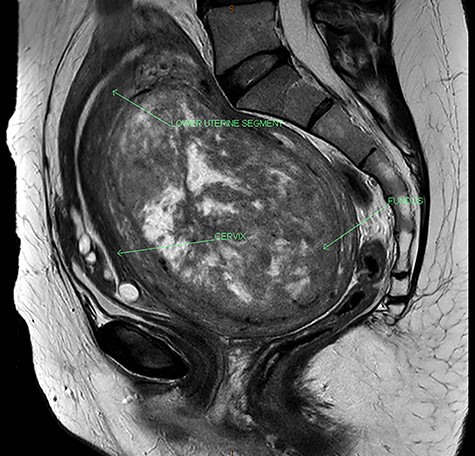

Her pelvic ultrasound showed a large posterior intramural leiomyoma, 112 × 72 × 89 mm, distending the uterus posteriorly and does not breach the subserosa surface. The endometrium has a normal contour. In view of the rapid onset and worsening of her symptoms, a pelvic MRI was performed to further characterize the uterine lesion, also to detect any regional lymphadenopathy. The magnetic resonance imaging (MRI) demonstrated a very large uterine fundal leiomyoma measuring 13 × 10.3 × 7.6 cm, displacing and distorting the other uterine structures in the setting of a retroflexed and retroverted uterus (Fig. 1). There is elongation of the lower uterine segment. The cervix is displaced anteriorly, while the bladder and bowel are compressed. No evidence of parametrical infiltration or regional lymphadenopathy was seen.

MRI of the pelvis showing acutely retroflexed uterus with the fundus occupying the pouch of Douglas.